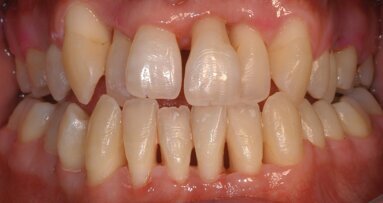

Un homme de 55 ans en bonne santé, se plaignait de mauvaise haleine et de saignements récurrents. L’examen clinique a montré un saignement au sondage (BOP) avec des profondeurs de poche au sondage (PPD) de 5 à 6 mm (Fig. 1), des dents stables sans mobilité, et l’exsudation. La radiographie a révélé une perte osseuse verticale et horizontale (Fig. 2). Par conséquent, ce cas a été classé en tant que parodontite sévère. L’hygiéniste dentaire a commencé le traitement avec un détartrage et surfaçage radiculaire, puis a montré au patient comment pratiquer une bonne hygiène buccale. Six semaines plus tard la situation a été réévaluée : il n’y avait eu aucune amélioration clinique significative ni des PPD ni du BOP. Nous avons décidé d’effectuer une intervention chirurgicale à lambeau ouvert.

Des études montrent que le tartre sous-gingival peut être enlevé avec un laser ER:YAG.15–19 Le patient est revenu le lendemain et ne ressentait plus de douleur, et aucun gonflement n’a été observé.3, 9 Il a été prévu de revoir le patient pour un traitement d’entretien à intervalles de trois mois pendant une période de trois ans. Un an et trois mois après les interventions, le niveau d’attache clinique (CAL), la PPD, la récession, une évaluation de la quantité de plaque et des saignements, ont été effectués. Aucune profondeur des poches parodontales ne dépassait 3 mm. Les photos présentées dans les figures 1 à 12 décrivent les différentes étapes de cette étude de cas.